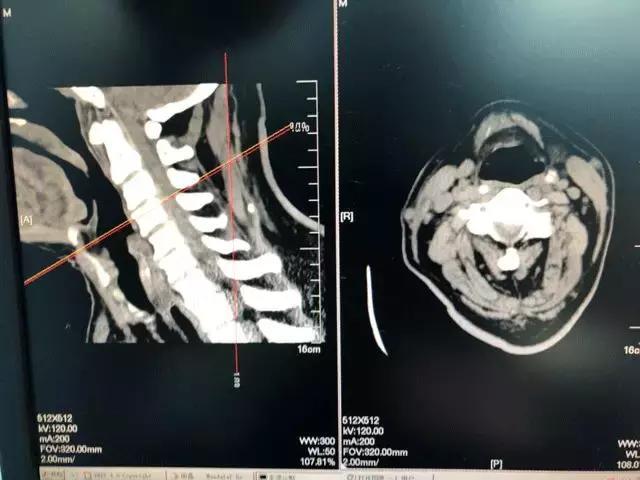

术前患者

颈椎间盘突出物高度移位压迫脊髓

四肢麻木无力且行走困难

处在瘫痪边缘

经检查确诊为脊髓型颈椎病,影像学检查提示患者颈3-4椎间盘突出,且高度移位。因为患者突出的椎间盘向下移位,躲到了颈4椎体的后方,多家医院均建议患者行颈椎椎体次全切除减压融合开放手术。但患者年龄较大,且患有慢支肺气肿肺心病,不能耐受大手术。矛盾的是,如果不手术,将来又可能出现脊髓压迫日久导致瘫痪的情况。